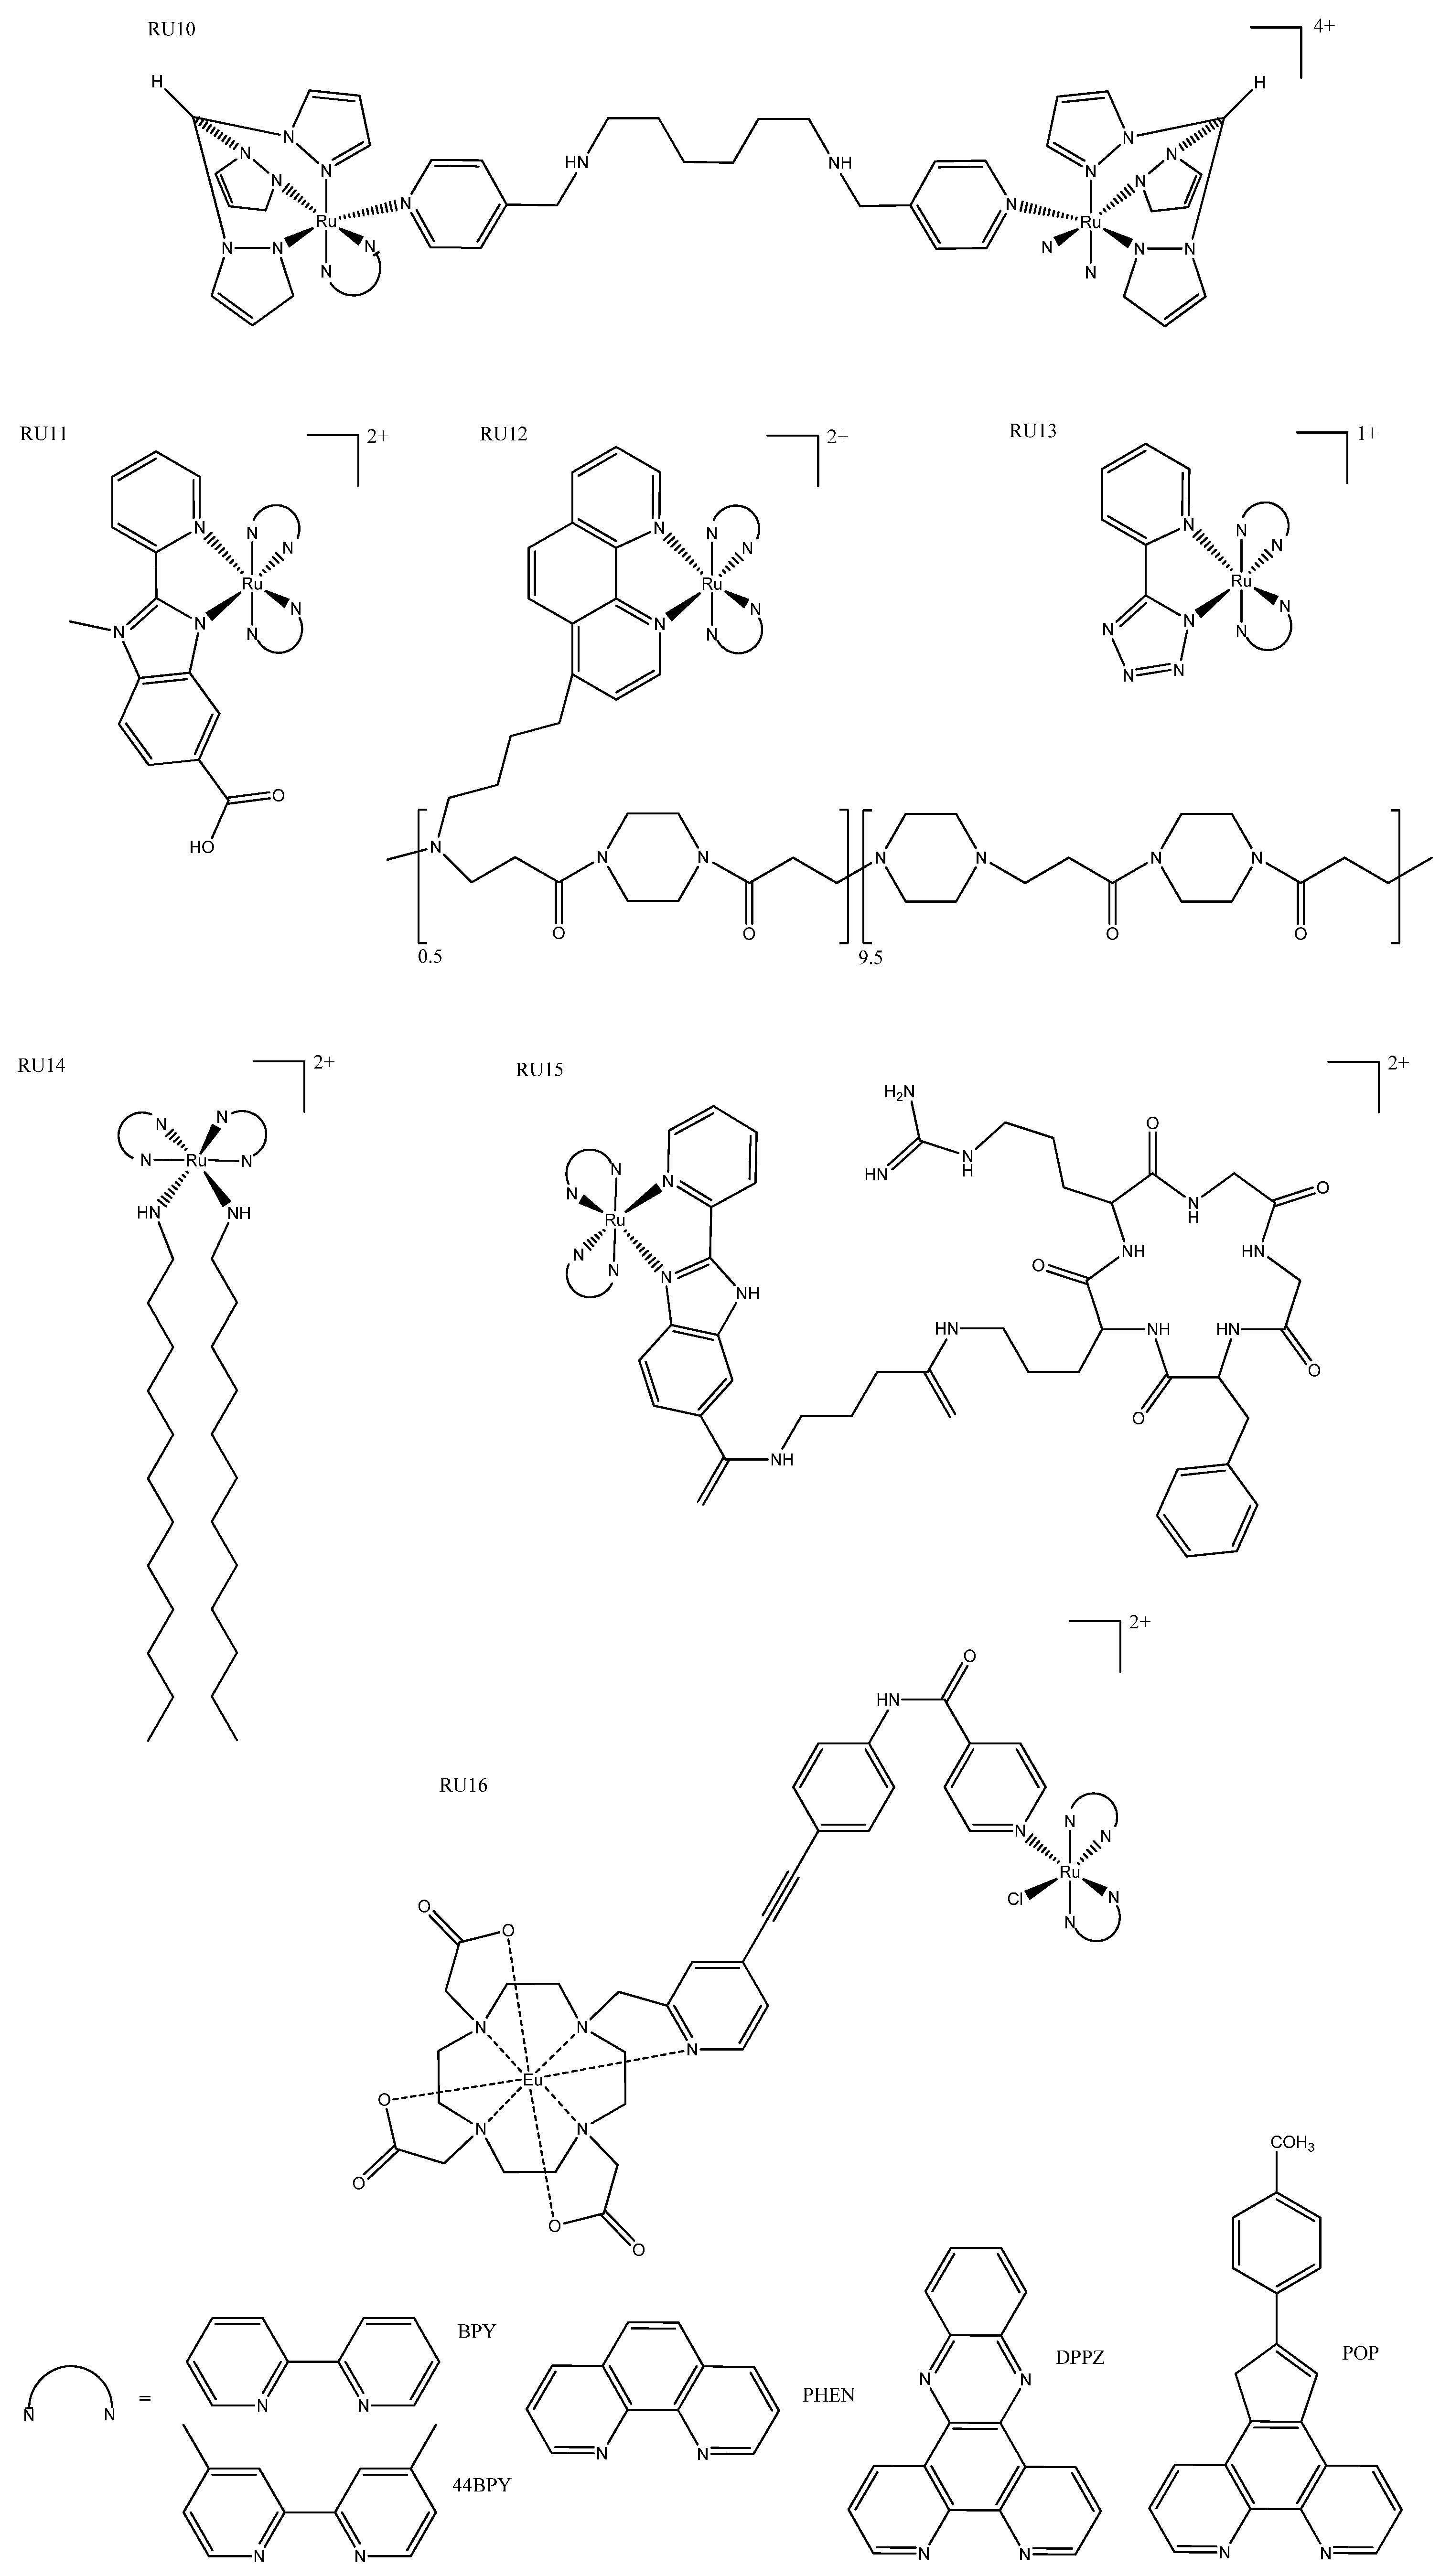

3. Ruthenium Complexes

3.4. Other

- Zhao, Z.; Hu, R.; Shi, H.; Wang, Y.; Ji, L.; Zhang, P.; Zhang, Q. Design of Ruthenium-Albumin Hydrogel for Cancer Therapeutics and Luminescent Imaging. J. Inorg. Biochem. 2019, 194, 19–25. [Google Scholar] [CrossRef]

- Mascheroni, L.; Dozzi, M.V.; Ranucci, E.; Ferruti, P.; Francia, V.; Salvati, A.; Maggioni, D. Tuning Polyamidoamine Design to Increase Uptake and Efficacy of Ruthenium Complexes for Photodynamic Therapy. Inorg. Chem. 2019, 58, 14586–14599. [Google Scholar] [CrossRef]

- Yang, J.; He, X.; Ke, Z.; Chen, J.; Zou, Z.; Wei, B.; Zou, D.; Zou, J. Two Photoactive Ru (II) Compounds Based on Tetrazole Ligands for Photodynamic Therapy. J. Inorg. Biochem. 2020, 210, 111127. [Google Scholar] [CrossRef]

- Nehru, S.; Veeralakshmi, S.; Kalaiselvam, S.; Subin David, S.P.; Sandhya, J.; Arunachalam, S. DNA Binding, Antibacterial, Hemolytic and Anticancer Studies of Some Fluorescent Emissive Surfactant-Ruthenium(II) Complexes. J. Biomol. Struct. Dyn. 2021, 39, 2242–2256. [Google Scholar] [CrossRef]

- Zhao, Z.; Zhang, X.; Li, C.-E.; Chen, T. Designing Luminescent Ruthenium Prodrug for Precise Cancer Therapy and Rapid Clinical Diagnosis. Biomaterials 2019, 192, 579–589. [Google Scholar] [CrossRef]

- Li, H.; Xie, C.; Lan, R.; Zha, S.; Chan, C.-F.; Wong, W.-Y.; Ho, K.-L.; Chan, B.D.; Luo, Y.; Zhang, J.-X.; et al. A Smart Europium-Ruthenium Complex as Anticancer Prodrug: Controllable Drug Release and Real-Time Monitoring under Different Light Excitations. J. Med. Chem. 2017, 60, 8923–8932. [Google Scholar] [CrossRef]

- Dos Santos, J.S.; Ramos, L.C.; Ferreira, L.P.; Campo, V.L.; de Rezende, L.C.D.; da Silva Emery, F.; Santana da Silva, R. Cytotoxicity, Cellular Uptake, and Subcellular Localization of a Nitrogen Oxide and Aminopropyl-β-Lactose Derivative Ruthenium Complex Used as Nitric Oxide Delivery Agent. Nitric Oxide Biol. Chem. 2019, 86, 38–47. [Google Scholar] [CrossRef]

- Weynand, J.; Diman, A.; Abraham, M.; Marcélis, L.; Jamet, H.; Decottignies, A.; Dejeu, J.; Defrancq, E.; Elias, B. Towards the Development of Photo-Reactive Ruthenium(II) Complexes Targeting Telomeric G-Quadruplex DNA. Chemistry 2018, 24, 19216–19227. [Google Scholar] [CrossRef]

| TDL1433 | 137 ± 3 | 1.9 ± 0.1 (400-700) | 525 | Optimized clinical procedure and completion of human clinical trials. | |||

| RU1 | 36.5 ± 3.0 | 3.1 ± 0.6 (420) | 620 | 420 | Photosensitizers for one- and two-photon PDT. | ||

| RU3 | 123 ± 3.62 | 3.77 ± 0.18 | 557/640 | 413 | Activated at multiple wavelengths; tracking possible both before and after photo treatment. | ||

| RU4a | 13 ± 2 | 0.47 ± 0.01 ** | 614 | 440 | Shows how modification of ancillary ligand and lipophilicity enhances therapeutic effect. | ||

| RU4b | 11 ± 3 | 2 ± 1 ** | 643 | 418 | |||

| RU6 | 83.1 ± 6.2 * | 34.1 ± 2.4 (460) | 500 | 355 | Slight variations in structure led to phototoxic or other photoactivated complexes. | ||

| RU6 | 31.3 ± 4.5 | 11.5 ± 2.5 (488) | 534 | 440 | Tagged with napthalamide derivative to target DNA. | ||

| RU8a | >300 | 12.0 ± 0.4 (633) | 805 | 540 | More lipophilic and absorption; more red-shifted than their non-cyclometallated counterparts. | ||

| RU8b | >300 | 16.6 ± 1.53 (625) | 728 | 550 | |||

| RU16 | 277.0 ± 7.1 | 32.5 ± 8.2 (488) | 570-750 | 350 | The linker could be irradiated at different wavelengths for different functionalization (prodrug activation or fluorescence). | ||

4. Platinum Complexes

4.1. Photosensitizers

4.2. Fluorescent Moiety

4.3. Cyclometallated Platinum Complexes

- Zhong, Y.-F.; Zhang, H.; Liu, W.-T.; Zheng, X.-H.; Zhou, Y.-W.; Cao, Q.; Shen, Y.; Zhao, Y.; Qin, P.Z.; Ji, L.-N.; et al. A Platinum(II)-Based Photosensitive Tripod as an Effective Photodynamic Anticancer Agent through DNA Damage. Chem. Eur. J. 2017, 23, 16442–16446. [Google Scholar] [CrossRef]

- Xue, X.; Zhu, C.; Chen, H.; Bai, Y.; Shi, X.; Jiao, Y.; Chen, Z.; Miao, Y.; He, W.; Guo, Z. A New Approach to Sensitize Antitumor Monofunctional Platinum(II) Complexes via Short Time Photo-Irradiation. Inorg. Chem. 2017, 56, 3754–3762. [Google Scholar] [CrossRef]

- Shi, H.; Clarkson, G.J.; Sadler, P.J. Dual Action Photosensitive Platinum(II) Anticancer Prodrugs with Photoreleasable Azide Ligands. Inorganica Chim. Acta 2019, 489, 230–235. [Google Scholar] [CrossRef]

- Thiabaud, G.; Arambula, J.F.; Siddik, Z.H.; Sessler, J.L. Photoinduced Reduction of PtIV within an Anti-Proliferative PtIV-Texaphyrin Conjugate. Chemistry 2014, 20, 8942–8947. [Google Scholar] [CrossRef] [Green Version]

- Lv, S.; Miao, Y.; Zheng, D.; Li, X.; Liu, D.; Song, F. Self-Assembled Platinum Supramolecular Metallacycles Based on a Novel TADF Photosensitizer for Efficient Cancer Photochemotherapy. Mol. Pharm. 2021, 18, 1229–1237. [Google Scholar] [CrossRef]

- Presa, A.; Vázquez, G.; Barrios, L.A.; Roubeau, O.; Korrodi-Gregório, L.; Pérez-Tomás, R.; Gamez, P. Photoactivation of the Cytotoxic Properties of Platinum(II) Complexes through Ligand Photoswitching. Inorg. Chem. 2018, 57, 4009–4022. [Google Scholar] [CrossRef] [PubMed] [Green Version]

- Laranjo, M.; Aguiar, M.C.; Pereira, N.A.M.; Brites, G.; Nascimento, B.F.O.; Brito, A.F.; Casalta-Lopes, J.; Gonçalves, A.C.; Sarmento-Ribeiro, A.B.; Pineiro, M.; et al. Platinum(II) Ring-Fused Chlorins as Efficient Theranostic Agents: Dyes for Tumor-Imaging and Photodynamic Therapy of Cancer. Eur. J. Med. Chem. 2020, 200, 112468. [Google Scholar] [CrossRef] [PubMed]

- Li, S.-Y.; Xie, B.-R.; Cheng, H.; Li, C.-X.; Zhang, M.-K.; Qiu, W.-X.; Liu, W.-L.; Wang, X.-S.; Zhang, X.-Z. A Biomimetic Theranostic O2-Meter for Cancer Targeted Photodynamic Therapy and Phosphorescence Imaging. Biomaterials 2018, 151, 1–12. [Google Scholar] [CrossRef] [PubMed]

- Xu, J.; Kuang, Y.; Lv, R.; Yang, P.; Li, C.; Bi, H.; Liu, B.; Yang, D.; Dai, Y.; Gai, S.; et al. Charge Convertibility and near Infrared Photon Co-Enhanced Cisplatin Chemotherapy Based on Upconversion Nanoplatform. Biomaterials 2017, 130, 42–55. [Google Scholar] [CrossRef]

- Zhang, Q.; Wang, S.; Zhu, Y.; Zhang, C.; Cao, H.; Ma, W.; Tian, X.; Wu, J.; Zhou, H.; Tian, Y. Functional Platinum(II) Complexes with Four-Photon Absorption Activity, Lysosome Specificity, and Precise Cancer Therapy. Inorg. Chem. 2021, 60, 2362–2371. [Google Scholar] [CrossRef]

- Kuang, G.; Lu, H.; He, S.; Xiong, H.; Yu, J.; Zhang, Q.; Huang, Y. Near-Infrared Light-Triggered Polyprodrug/SiRNA Loaded Upconversion Nanoparticles for Multi-Modality Imaging and Synergistic Cancer Therapy. Adv. Healthc. Mater. 2021, 10. [Google Scholar] [CrossRef]

- Sun, Y.; Ding, F.; Chen, Z.; Zhang, R.; Li, C.; Xu, Y.; Zhang, Y.; Ni, R.; Li, X.; Yang, G.; et al. Melanin-Dot-Mediated Delivery of Metallacycle for NIR-II/Photoacoustic Dual-Modal Imaging-Guided Chemo-Photothermal Synergistic Therapy. Proc. Natl. Acad. Sci. USA 2019, 116, 16729–16735. [Google Scholar] [CrossRef] [PubMed] [Green Version]

- Wang, H.; Lv, B.; Tang, Z.; Zhang, M.; Ge, W.; Liu, Y.; He, X.; Zhao, K.; Zheng, X.; He, M.; et al. Scintillator-Based Nanohybrids with Sacrificial Electron Prodrug for Enhanced X-Ray-Induced Photodynamic Therapy. Nano Lett. 2018, 18, 5768–5774. [Google Scholar] [CrossRef] [PubMed]

- Şahin, Ö.; Özdemir, Ü.Ö.; Seferoğlu, N.; Genc, Z.K.; Kaya, K.; Aydıner, B.; Tekin, S.; Seferoğlu, Z. New Platinum (II) and Palladium (II) Complexes of Coumarin-Thiazole Schiff Base with a Fluorescent Chemosensor Properties: Synthesis, Spectroscopic Characterization, X-ray Structure Determination, in vitro Anticancer Activity on Various Human Carcinoma Cell Lines and Computational Studies. J. Photochem. Photobiol. B 2018, 178, 428–439. [Google Scholar] [CrossRef] [PubMed]

- Schlagintweit, J.F.; Jakob, C.H.G.; Meighen-Berger, K.; Gronauer, T.F.; Weigert Muñoz, A.; Weiß, V.; Feige, M.J.; Sieber, S.A.; Correia, J.D.G.; Kühn, F.E. Fluorescent Palladium(II) and Platinum(II) NHC/1,2,3-Triazole Complexes: Antiproliferative Activity and Selectivity against Cancer Cells. Dalton Trans. 2021, 50, 2158–2166. [Google Scholar] [CrossRef]

- Hadian Rasanani, S.; Eslami Moghadam, M.; Soleimani, E.; Divsalar, A.; Ajloo, D.; Tarlani, A.; Amiri, M. Anticancer Activity of New Imidazole Derivative of 1R,2R-Diaminocyclohexane Palladium, and Platinum Complexes as DNA Fluorescent Probes. J. Biomol. Struct. Dyn. 2018, 36, 3058–3076. [Google Scholar] [CrossRef]

- Lo, A.T.S.; Bryce, N.S.; Klein, A.V.; Todd, M.H.; Hambley, T.W. Novel Polyamide Amidine Anthraquinone Platinum(II) Complexes: Cytotoxicity, Cellular Accumulation, and Fluorescence Distributions in 2D and 3D Cell Culture Models. J. Biol. Inorg. Chem. 2021, 26, 217–233. [Google Scholar] [CrossRef]

- Millán, G.; Giménez, N.; Lara, R.; Berenguer, J.R.; Moreno, M.T.; Lalinde, E.; Alfaro-Arnedo, E.; López, I.P.; Piñeiro-Hermida, S.; Pichel, J.G. Luminescent Cycloplatinated Complexes with Biologically Relevant Phosphine Ligands: Optical and Cytotoxic Properties. Inorg. Chem. 2019, 58, 1657–1673. [Google Scholar] [CrossRef]

- Lázaro, A.; Balcells, C.; Quirante, J.; Badia, J.; Baldomà, L.; Ward, J.S.; Rissanen, K.; Font-Bardia, M.; Rodríguez, L.; Crespo, M.; et al. Luminescent PtII and PtIV Platinacycles with Anticancer Activity Against Multiplatinum-Resistant Metastatic CRC and CRPC Cell Models. Chemistry 2020, 26, 1947–1952. [Google Scholar] [CrossRef]

| Pt Complex | IC50 (μM) | Luminescence | Special Features | ||

|---|---|---|---|---|---|

| Dark (Cell Line) | Light (Irradiation nm) | λEm(max) (nm) | λEx(max) (nm) | ||

| PT2 | >50 (HeLa) | 7.4 ± 0.3(635) | 550–650 | 566 | Positively charged Pt(II) center not only provided the cell membrane with an anchoring ability, but also made the complex a mild photosensitizer. |

| PT6 | >75 (A375) | 3.1 ± 0.2(365) | 470 | 300 | Light-mediated conversion from open to closed. |

| PT9 | None (HeLa) | “Increased” (NIR) * | Negatively charged in normal physiological conditions, and converted to positive charge in acidic tumor extracellular microenvironments. | ||

| PT15 | 410, 470 | 300 | DNA groove via hydrogenic or hydrophobic interaction. | ||

| PT16 | 16.2 ± 0.3 (MDA-MB-231) | 615 | 525 | Spheroid penetration. | |

| PT17a | 20.29 ± 2.10 (HeLa) | 400 | 475 | Shows potential as an anti-tubulin agent, and also provides useful information for our understanding of the mechanism responsible for the cytotoxic activity caused by these cyclometallated complexes. | |

| PT17b | 12.45 ± 2.50 (HeLa) | 388 | 458 | Selective generation of oxidative stress in cancer cells over noncancerous cells. | |